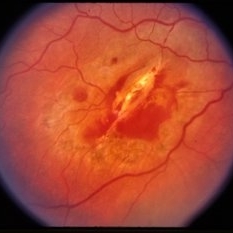

Pre-retinal and retinal hemorrhage with foreign body.

Condition/keywords: intraocular foreign body, trauma